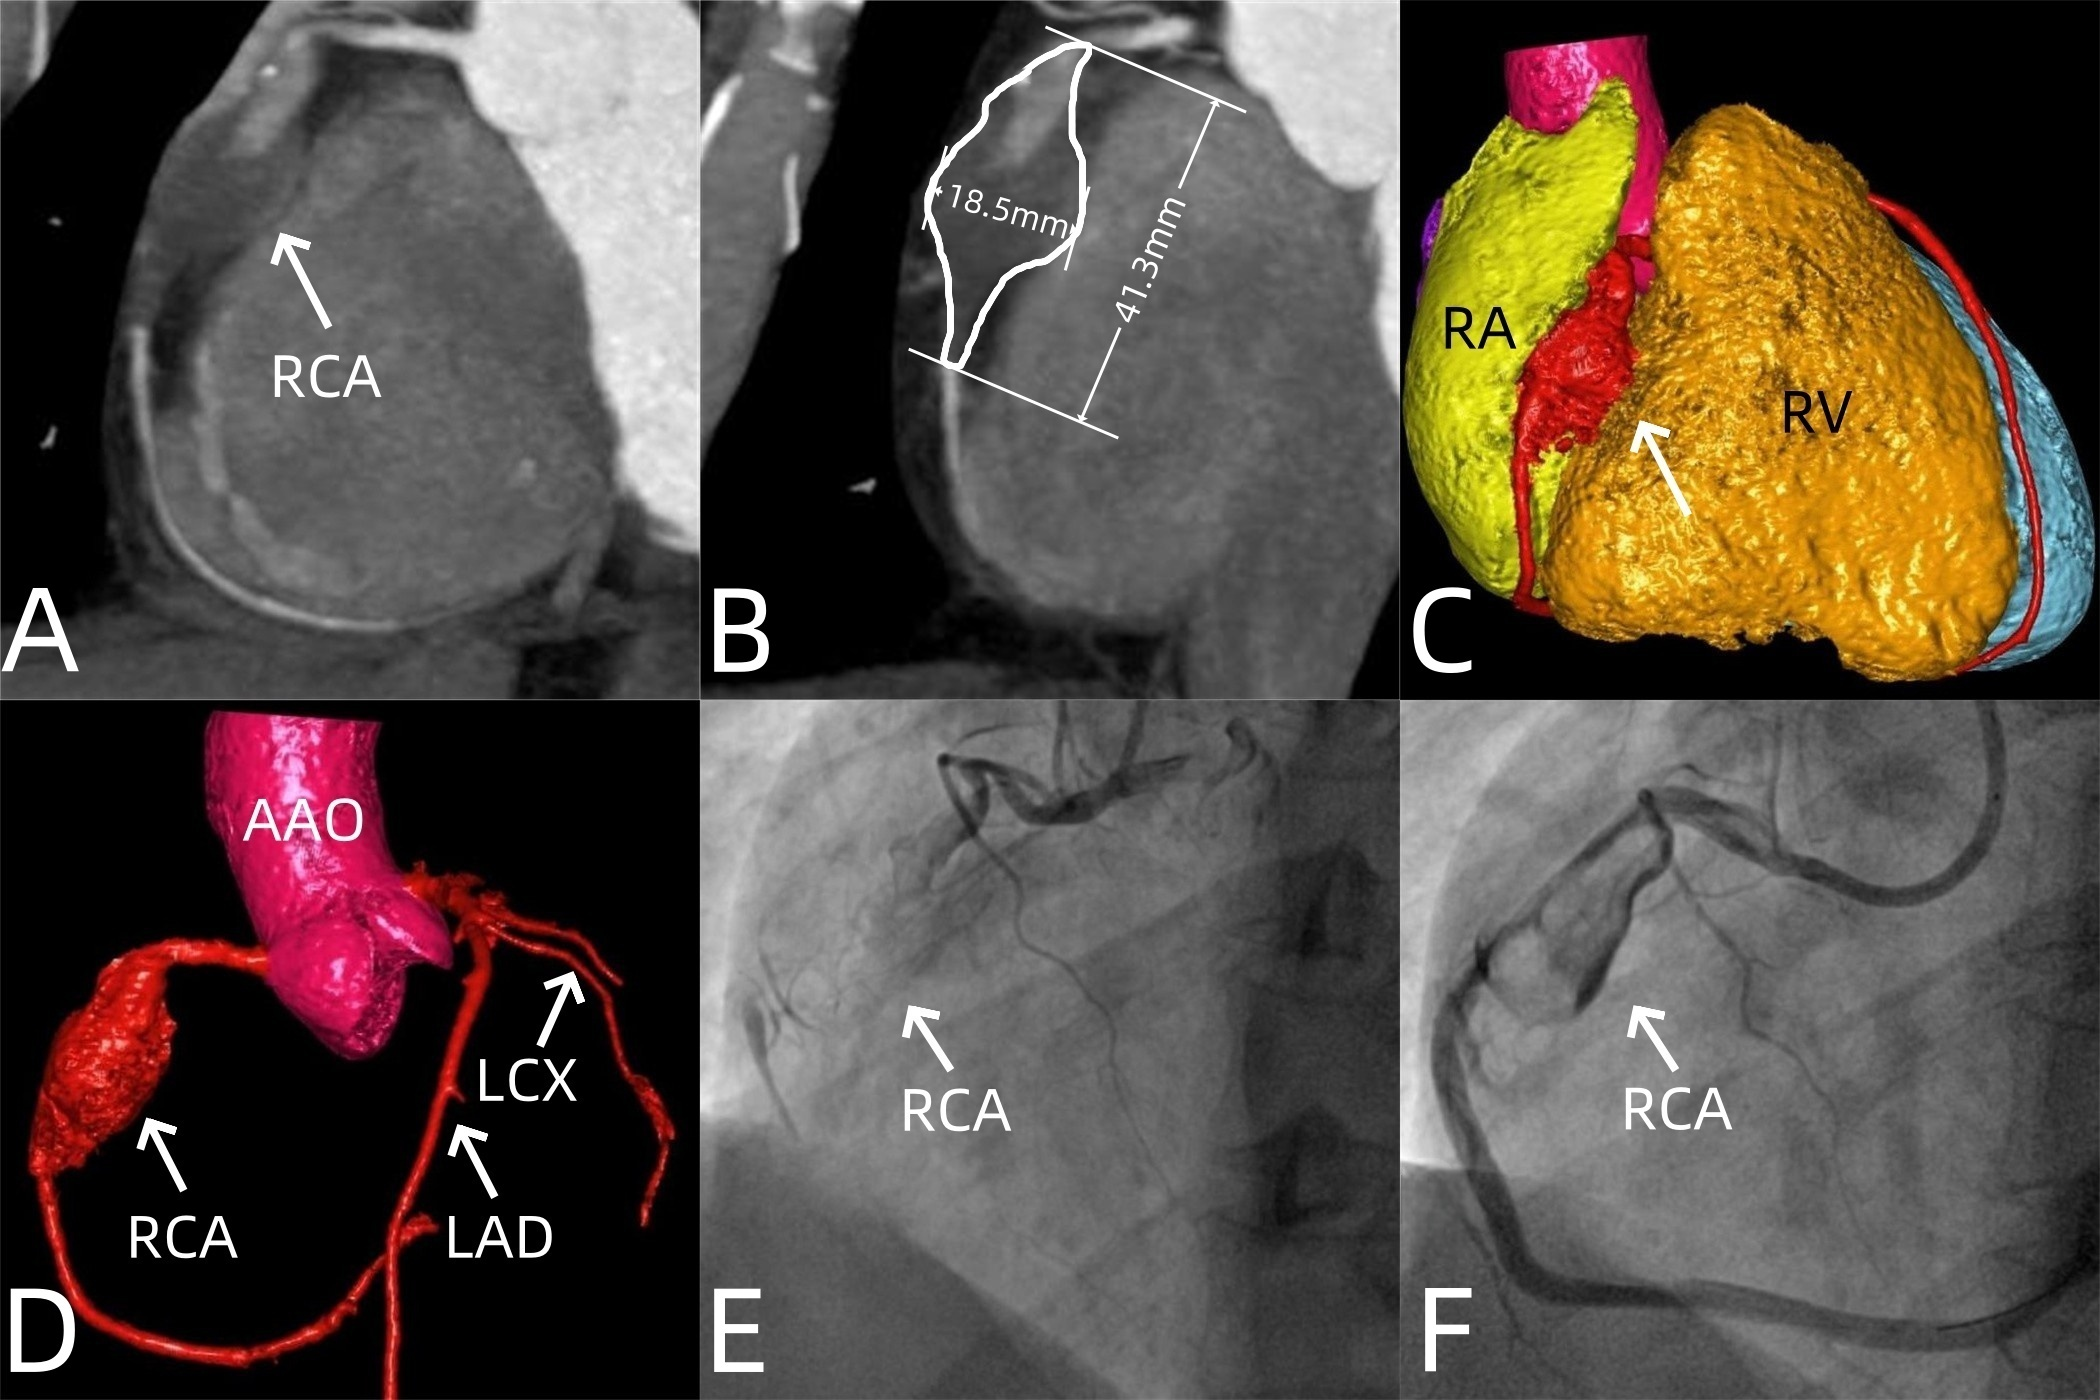

A 36-year-old man presented with chest pain lasting for half a month. Laboratory tests showed mildly elevated high-sensitivity troponin I (0.0883 ng/mL) and high-sensitivity troponin I-c (88 ng/L), along with an elevated high-sensitivity C-reactive protein (64.61 mg/L). Rheumatology-related antibodies were negative. An electrocardiogram indicated an inferior wall myocardial infarction. Coronary computed tomography angiography (CTA) revealed a fusiform aneurysm in the middle segment of the right coronary artery (RCA) (Figure). Its maximum cross-section measured 18.5 × 17.5 mm, with an affected segment length of 41.3 mm. Thrombosis was present in the aneurysm, and there were segmental occlusions in part of the aneurysm and distal lumen. Coronary angiography confirmed the CTA findings (Figure, Videos 1 and 2). After multidisciplinary team discussion, the patient underwent percutaneous transluminal coronary angioplasty with drug-coated balloon intervention in the RCA. The postoperative course was uneventful, and the patient was discharged on postoperative day 7.